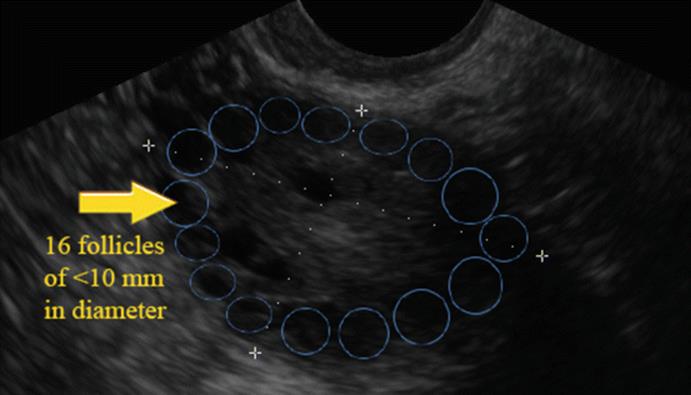

Polycystic ovarian morphology (PCOM) is an important element for the diagnosis of polycystic ovarian syndrome in adult women. The Rotterdam consensus defined PCOM as the presence of 12 or more follicles of 2–9 mm in diameter and/or an ovarian volume greater than 10 mL in at least 1 ovary (Fig. 5.1).

Fig. 5.1

Polycystic ovarian morphology